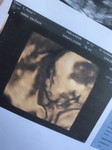

กำลังจะเป็นแม่

Vàngกำลังจะเป็นแม่